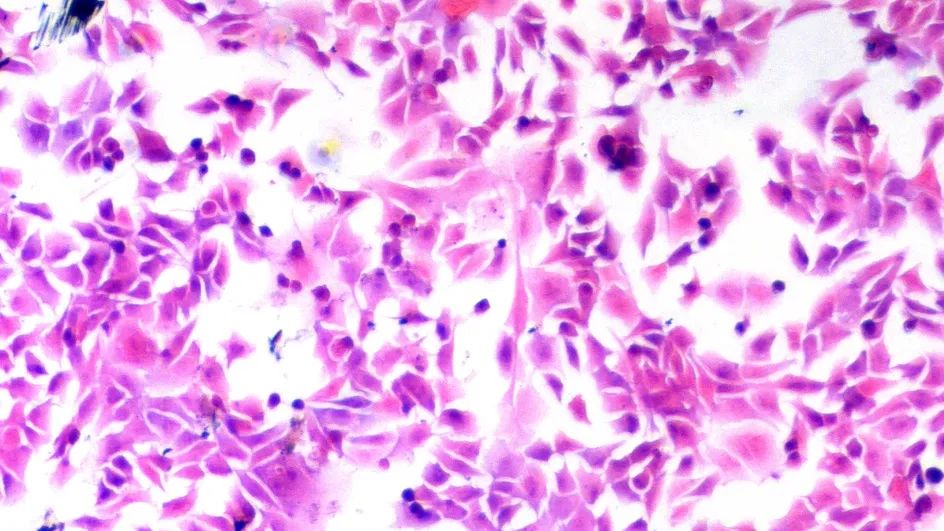

※实验结果示例:

正常情况下,苏木素染细胞核为蓝色,细胞质着色为粉红色。

,经第8次传代后,平滑肌细胞仍生长迅速,未见衰老迹象。倒置显微镜下观察均呈“谷和峰”样结构(图1 对照组2周的细胞;图2 实验组培养2周的细胞)。细胞爬片HE染色见膀胱平滑肌细胞细胞核呈两端钝圆的卵圆形平滑肌细胞核型。电镜检查可见平滑肌细胞密班结构。免疫组化染色检测α-actin呈阳性反应。从细胞爬片HE染色和免疫组化染色检测α-actin呈阳性反应中我们发现该方法所的膀胱平滑肌细胞的纯度几乎99%。 图1 对照组2周的细胞图2 实验组培养2周的细胞